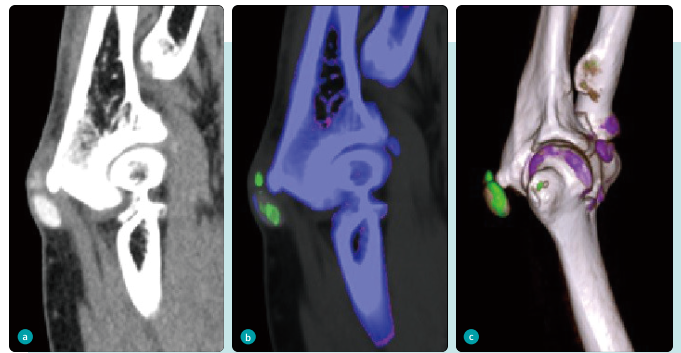

左图为右肘关节矢状位显示肘关节旁稍高密度结节,中图和右图为双能量痛风分析后右肘关节矢状位及VR重建显示肘关节旁结节绿染,与尿酸单钠沉积一致,结果解释为痛风石。